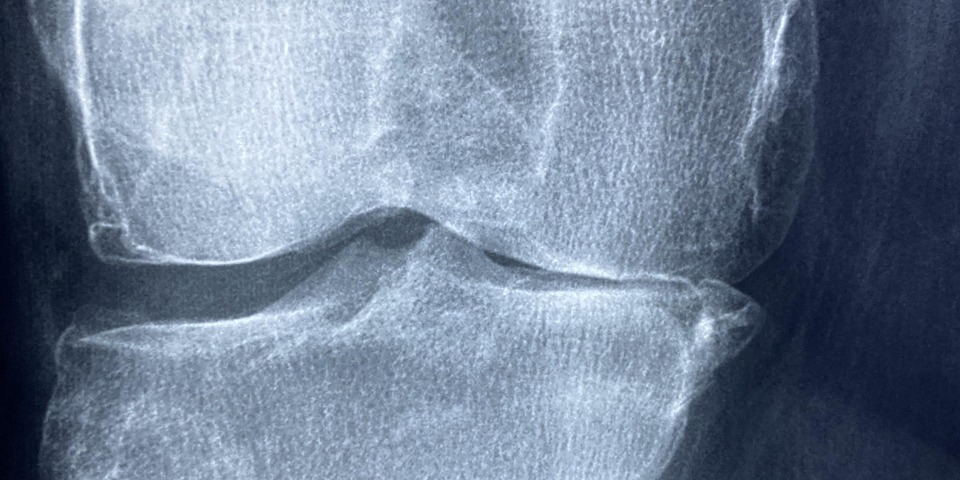

– Diagnostik mit bildgebenden Verfahren (z. B. Röntgen, MRT, Ultraschall)